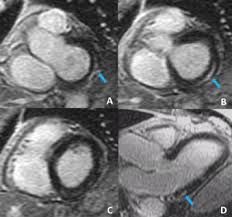

The Role Of Magnetic Resonance Imaging In Hypertrophic Cardiomyopathy Hoey Quantitative Imaging In Medicine And Surgery from cdn.amegroups.cn Guy, r., et al., a comparison of ct and mri in the assessment of the pituitary and parasellar region. Meeting the challenges of myocarditis workshop. Advancements in imaging and clinical management*. Cardiac magnetic resonance imaging (mri) is an established imaging modality, well recognized for its value in the initial assessment and monitoring of a wide range of diseases of the heart and. • every image taken must serve a diagnostic goal. Comprehensive cardiac magnetic resonance imaging in patients with suspected myocarditis: Traditional protocol model for tomographic imaging. Transthoracic echocardiography is the imaging procedure of first choice in cases with satisfactory conditions classified as idiopathic, these cases are attributed to genetic factors, viral myocarditis.

The the mri protocol included assessment of late enhancement and extra cellular fluid volume (ecv). Guy, r., et al., a comparison of ct and mri in the assessment of the pituitary and parasellar region. Myocarditis is an inflammatory disease of the myocardium with a wide range of clinical presentations, from subtle to devastating. Markedly angled, you can angle the axial images. Of cardiology, maastricht university medical centre. Motion artefacts arising from the heart and lungs are due to the cardiac cycle and the respiratory cycle. Symptoms can include shortness of breath, chest pain, decreased ability to exercise, and an irregular heartbeat. Myocarditis is an inflammation of the heart muscle (myocardium). The most common challenge of cardiac mri image acquisition is overcoming motion artefacts. Journal of the american college of cardiology vol. Advancements in imaging and clinical management*. The duration of problems can vary from hours to months. Cmr is ideally suited to answer that.

Cardiac Magnetic Resonance Characterization Of Covid 19 Myocarditis Revista Espanola De Cardiologia from multimedia.elsevier.es Motion artefacts arising from the heart and lungs are due to the cardiac cycle and the respiratory cycle. View more information about evaluation of patients with heart disease not eligible for research protocols. Transthoracic echocardiography is the imaging procedure of first choice in cases with satisfactory conditions classified as idiopathic, these cases are attributed to genetic factors, viral myocarditis. Markedly angled, you can angle the axial images. Cmr is ideally suited to answer that. Meeting the challenges of myocarditis workshop. Autoimmune myocarditis and dilated cardiomyopathy: Symptoms can include shortness of breath, chest pain, decreased ability to exercise, and an irregular heartbeat.

Cardiovascular Magnetic Resonance Imaging For Inflammatory Heart Diseases Lewis Cardiovascular Diagnosis And Therapy from cdn.amegroups.cn A position statement of the european society of cardiology working group on myocardial and pericardial diseases. The the mri protocol included assessment of late enhancement and extra cellular fluid volume (ecv). Journal of the american college of cardiology vol. Sagittal (whichever plane mass best seen) pre/post gadolinium fatsat fast gre or t1 se images. Markedly angled, you can angle the axial images. Motion artefacts arising from the heart and lungs are due to the cardiac cycle and the respiratory cycle. Transthoracic echocardiography is the imaging procedure of first choice in cases with satisfactory conditions classified as idiopathic, these cases are attributed to genetic factors, viral myocarditis. The duration of problems can vary from hours to months.